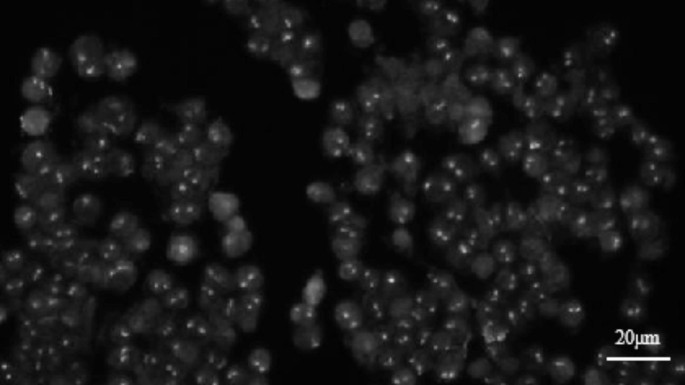

The inverted fluorescence microscope used was an OLYMPUS IX83, equipped with a fluorescence illumination system and widefield imaging modality. The objective lens was an OLYMPUS LUCPLFLN 60X with a numerical aperture (N.A) of 0.7 and a magnification of 60. The detector used for image acquisition was a QIMAGING optiMOS camera, which is a type of sCMOS. This combination of camera and objective lens is designed to balance imaging resolution, the requirements of the detection task, and the availability of equipment under the current experimental conditions. All FISH images and biological experiments in this study were conducted and provided by professionals from our laboratory. Each pixel corresponds to an actual distance of approximately 0.1 μm, and each FISH spot is about 5 pixels in size. Figure 1 shows representative images along with their scalebars.